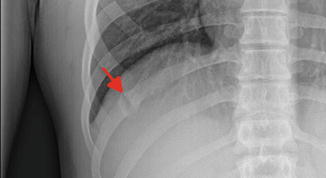

외상의 골절과는 다르게 여러개의 뼈가 부러지는 형태가 아닌 단일뼈가 부러지는 형태의

피로골절 형태의 골절이 생기는 경우가 많습니다.

진단은 물론 X-ray 나 CT, bone scan 같은 영상검사로 하게 되지만

골절이 생긴 후에 회복이 되는 경우에도 엑스레이에는 유합된 흔적이 남을 수 있습니다.